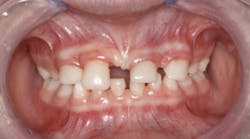

A nine-year-old female was referred to me by a local pediatric dentist (figure 1). The pediatric dentist felt she had reached the limit in what she could provide for the patient cosmetically. The patient had received only routine dental care and cosmetic bonding thus far. She was entering fourth grade in school and was becoming increasingly self-conscious about her smile (figure 2).